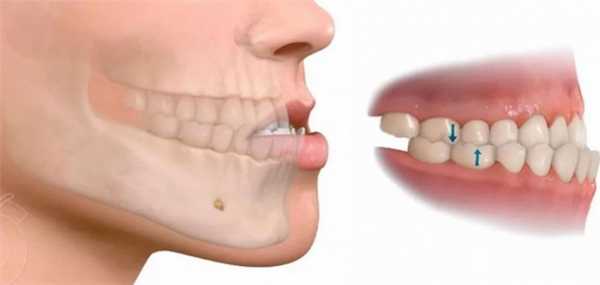

Неправильный прикус из-за нарушения роста челюстей может проявляться отклонением от нормального расположения зубов и повороту части зубов на одной из челюстей. Иногда резцы одной челюсти значительно перекрывают другую; в редких случаях формируется открытый неправильный прикус, когда резцы не смыкаются совсем. Виды неправильного прикуса:

- При глубоком прикусе верхние зубы закрывают нижнее более чем на половину.

КТ черепа (3D-рендеринг). Прогнатический прикус, зубы верхней челюсти (красная стрелка) выстоят кпереди, отсутствует контакт резцовых краев при смыкании.